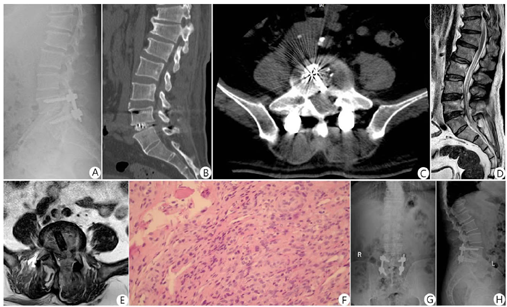

典型病例:57岁男性,顽固性腰痛1年、加重伴左下肢放射痛1个月。家中养羊、长期羊群接触史。体查示:L4~5棘突压痛、叩击痛;直腿抬高试验左侧阳性约40°、加强试验阳性约30°;左小腿前外侧、足背皮肤感觉减退。临床诊断为LBS,给予药物抗布鲁菌病、止痛及营养神经等保守治疗,腰痛症状无明显改善、且出现进行性左下肢麻木。行UBE下减压、清创、椎间融合联合经皮螺钉内固定术。术前、术中及术后影像学资料见图1,图2,图3。

注:A为术前MRI T2WI示:L4~5椎管层面硬膜外脓肿呈高信号;B为术前MRI横断面示:硬膜外脓肿压迫硬脊膜和神经根

注:A为侧位X线片示:内固定位置良好;B为CT矢状位示:植骨充分;C为CT横断面示:Cage位置良好;D为MRI T2WI示:椎管减压充分;E为MRI横断面示:病灶清除完全、减压充分及Cage位置良好;F为病理组织学示:非干酪样坏死肉芽肿性炎(HE染色,×400),可见大量淋巴细胞、单核细胞;G、H为术后14个月正、侧位X线片示植骨已融合、内固定位置良好